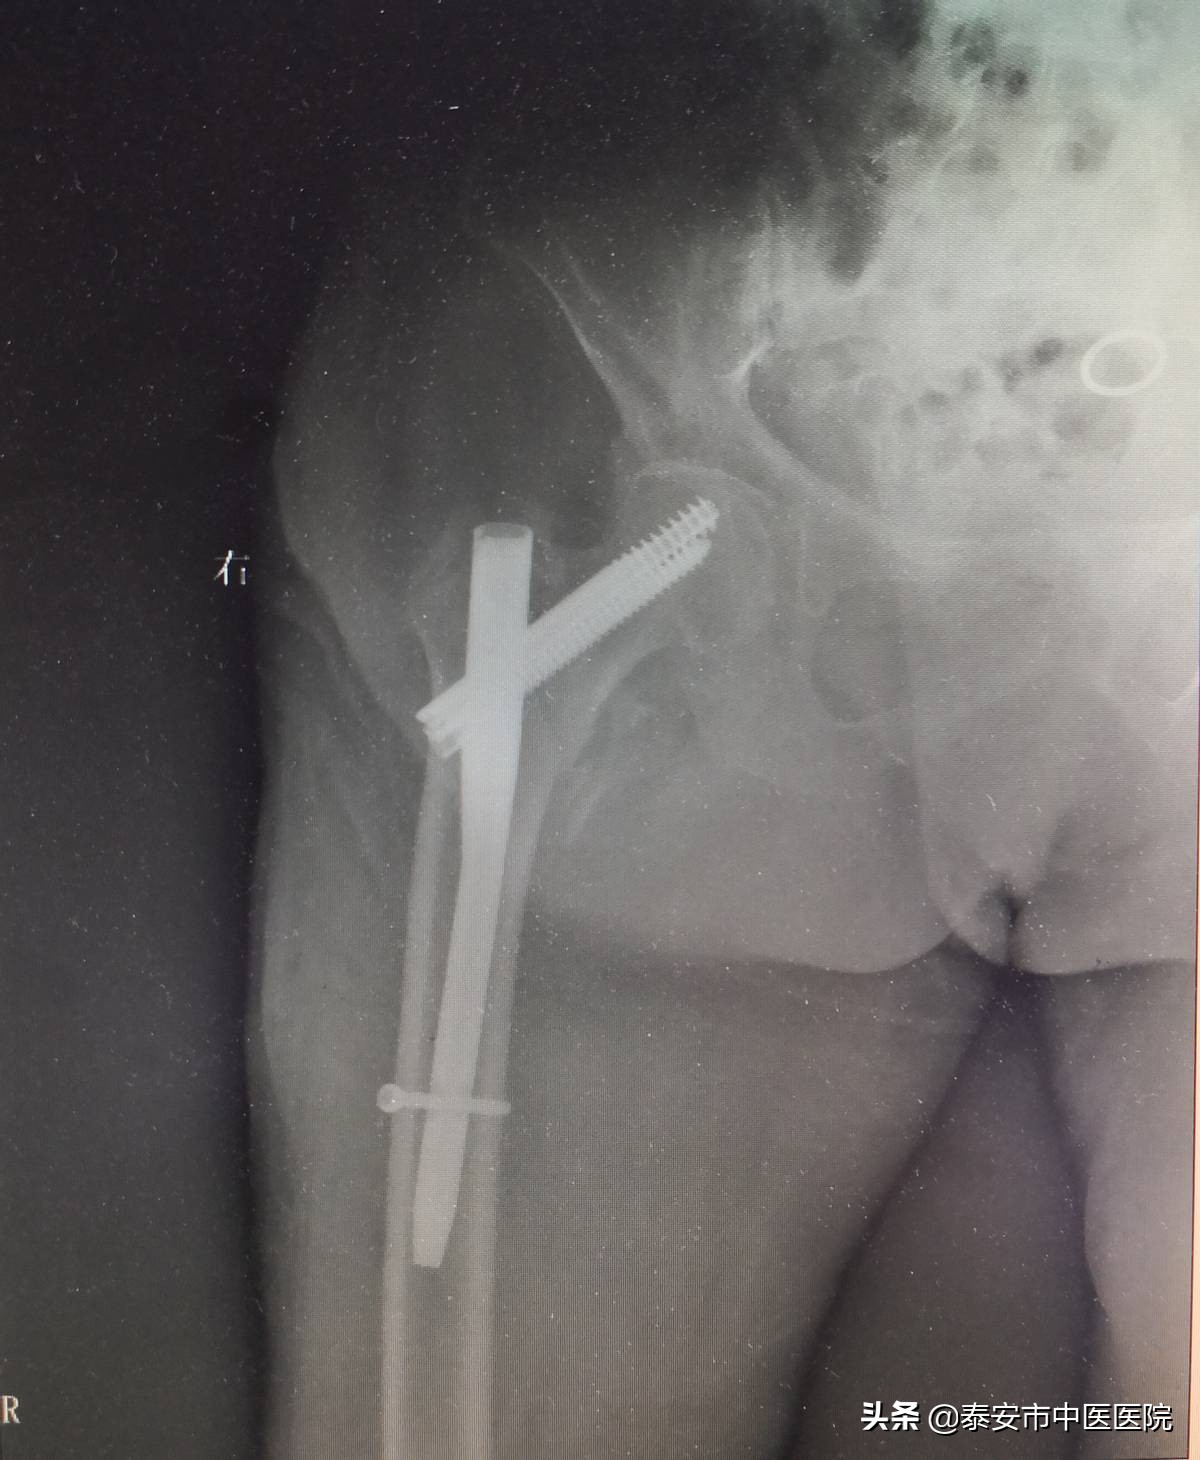

随着社会人口老龄化的发展,中老年人骨折发生率逐年上升,若治疗不当,会出现严重并发症,大大缩短患者的预期寿命,对于此类骨折,保守治疗由于卧床时间太长,易发生深静脉血栓,褥疮,肺部感染等并发症,危及患者生命。该室采用微创经皮内固定治疗股骨粗隆间骨折,具有手术创伤小(切口仅4cm左右),住院时间短,痛苦少,恢复快等优势特点,能让患者迅速恢复正常活动,减轻了患者家庭负担。

微创经皮内固定治疗股骨粗隆间骨折